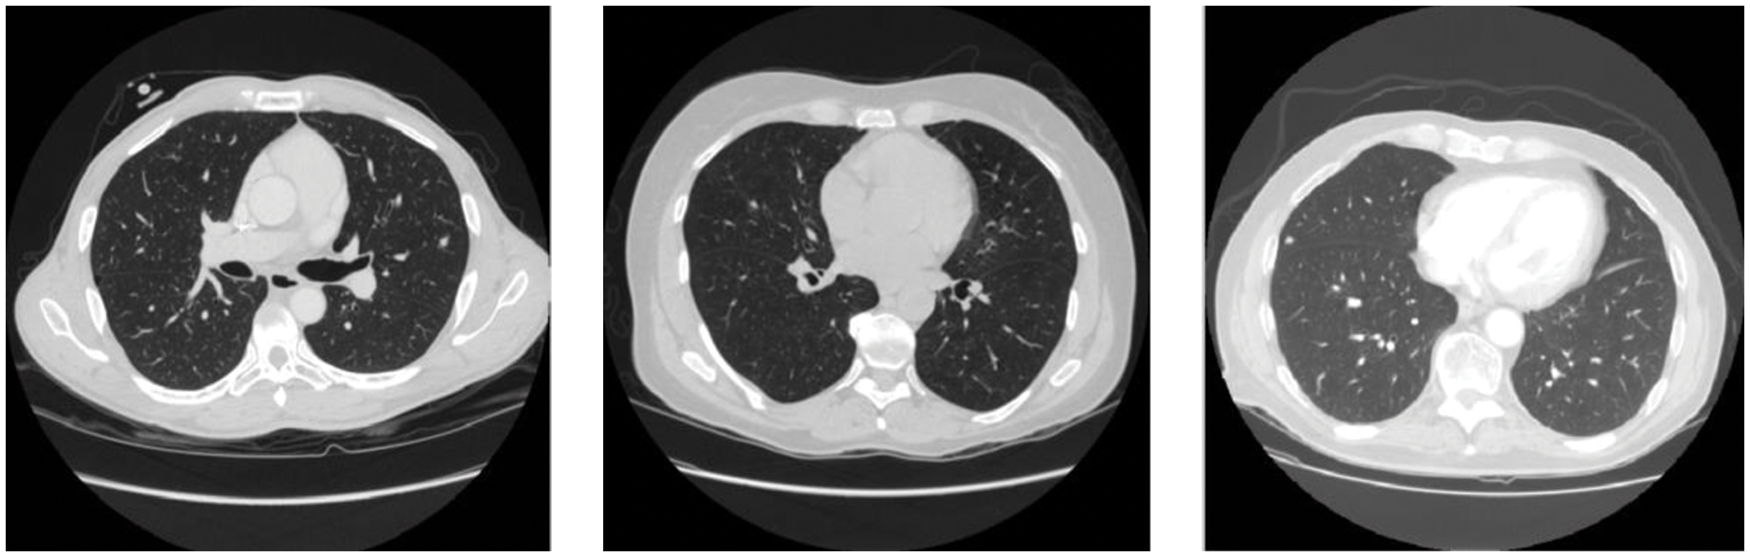

The CT lung images from LIDC [21,22] database images in the “Digital Imaging and Communications in Medicine” format are used to evaluate the AC-GAN-LCC system designed in the previous chapter. It is the world’s largest lung CT image database, collected from 1018 patients. Fig. 6 shows the sample images in the LIDC database. The size of CT scans in LIDC is 512 × 512 pixels. The layer thickness is between 1.25 and 3 mm, and 375,590 lung CT scans are available. From the annotations of four experienced radiologists, the information about the nodules is recorded in the extensible markup language file. Based on the ground truth data, the proposed system uses 14995 CT slices (7310 non-nodules and 7685 nodules) for the classification study. The performance of the AC-GAN-LCC system is validated using the k-fold (k = 10) cross-validation approach. Fig. 7 shows the procedure for the validation approach.

Figure 6: Sample CT scans in LIDC database